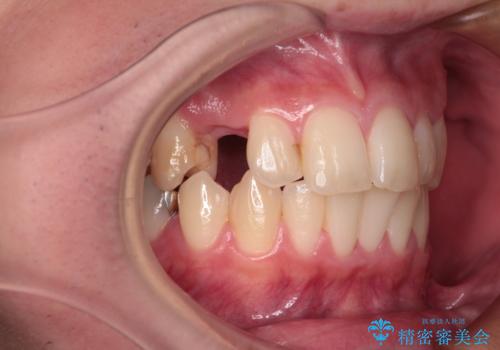

[ 乳歯の残存 ] 前歯のインプラント治療